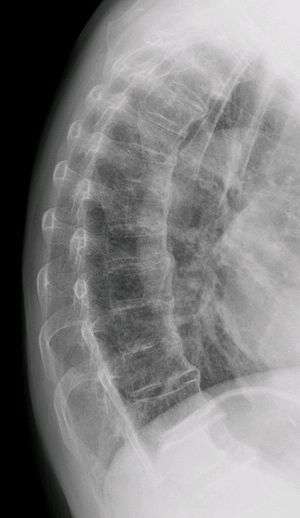

| Diffuse idiopathic skeletal hyperostosis. Woman of 80 years old, also with Th11 fracture. | |

Diffuse idiopathic skeletal hyperostosis (DISH) is a non-inflammatory spondyloarthropathy of the spine. It is characterized by spiny ankylosis and enthesopathy (ossification of the ligaments and entheses). It most commonly affects the thoracic and thoraco-lumbar spine, but involvement is variable and can include the entire spine.[1] The disc spaces, facet and sacroiliac joints remain unaffected. Diagnosis requires confluent ossification of at least four contiguous vertebral bodies.[1] Classically, advanced disease may have "melted candle wax" appearance along the spine on radiographic studies.[2]

The exact cause is unknown. Mechanical factors, dietary and long term use of some antidepressants may be of significance. There is a correlation between these factors but not a cause or effect. The distinctive radiological feature of DISH is the continuous linear calcification along the antero-medial aspect of the thoracic spine. The disease is usually found in people in their 60s and above, and is extremely rare in people in their 40s and 30s. The disease can spread to any joint of the body, affecting the neck, shoulders, ribs, hips, pelvis, knees, ankles, and hands. The disease is not fatal, however some associated complications can lead to death. Complications include paralysis, dysphagia (the inability to swallow), and pulmonary infections. Although DISH manifests in a similar manner to ankylosing spondylitis, these two are totally separate diseases. Ankylosing spondylitis is a genetic disease with identifiable marks, and affects organs. DISH has no indication of a genetic link, and does not affect organs other than the lungs, which is only indirect due to the fusion of the rib cage.[3]